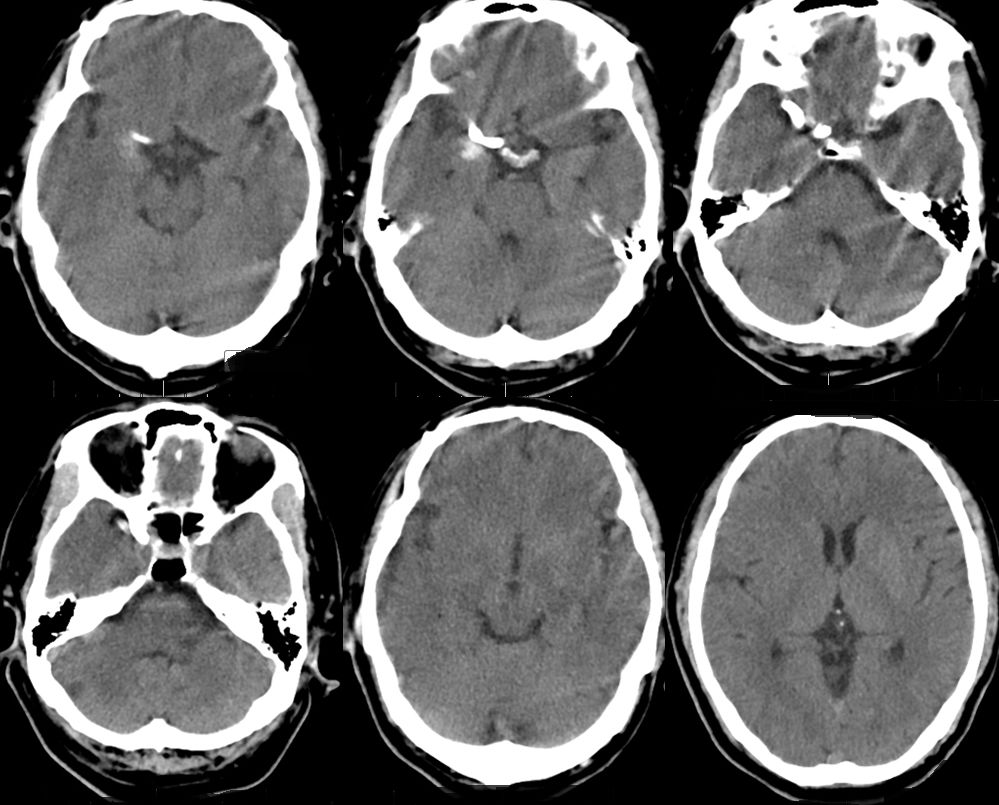

2、术后18小时急诊DSA(图六)。

治疗颅内动脉瘤新型密网支架,pipeline治疗椎动脉夹层动脉瘤

图六

DSA术前后对比(图七)。

图七